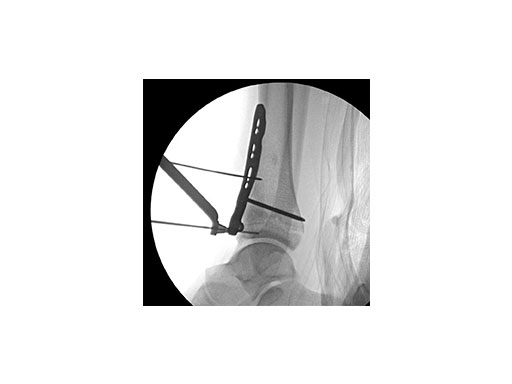

Surgeons performed an anterolateral surgical approach and distracted the joint using the distraction clamp and osteotome (Fig 2). The fracture was fixated with a VA-LCP Anterolateral Distal Tibia Plate (Fig 35).